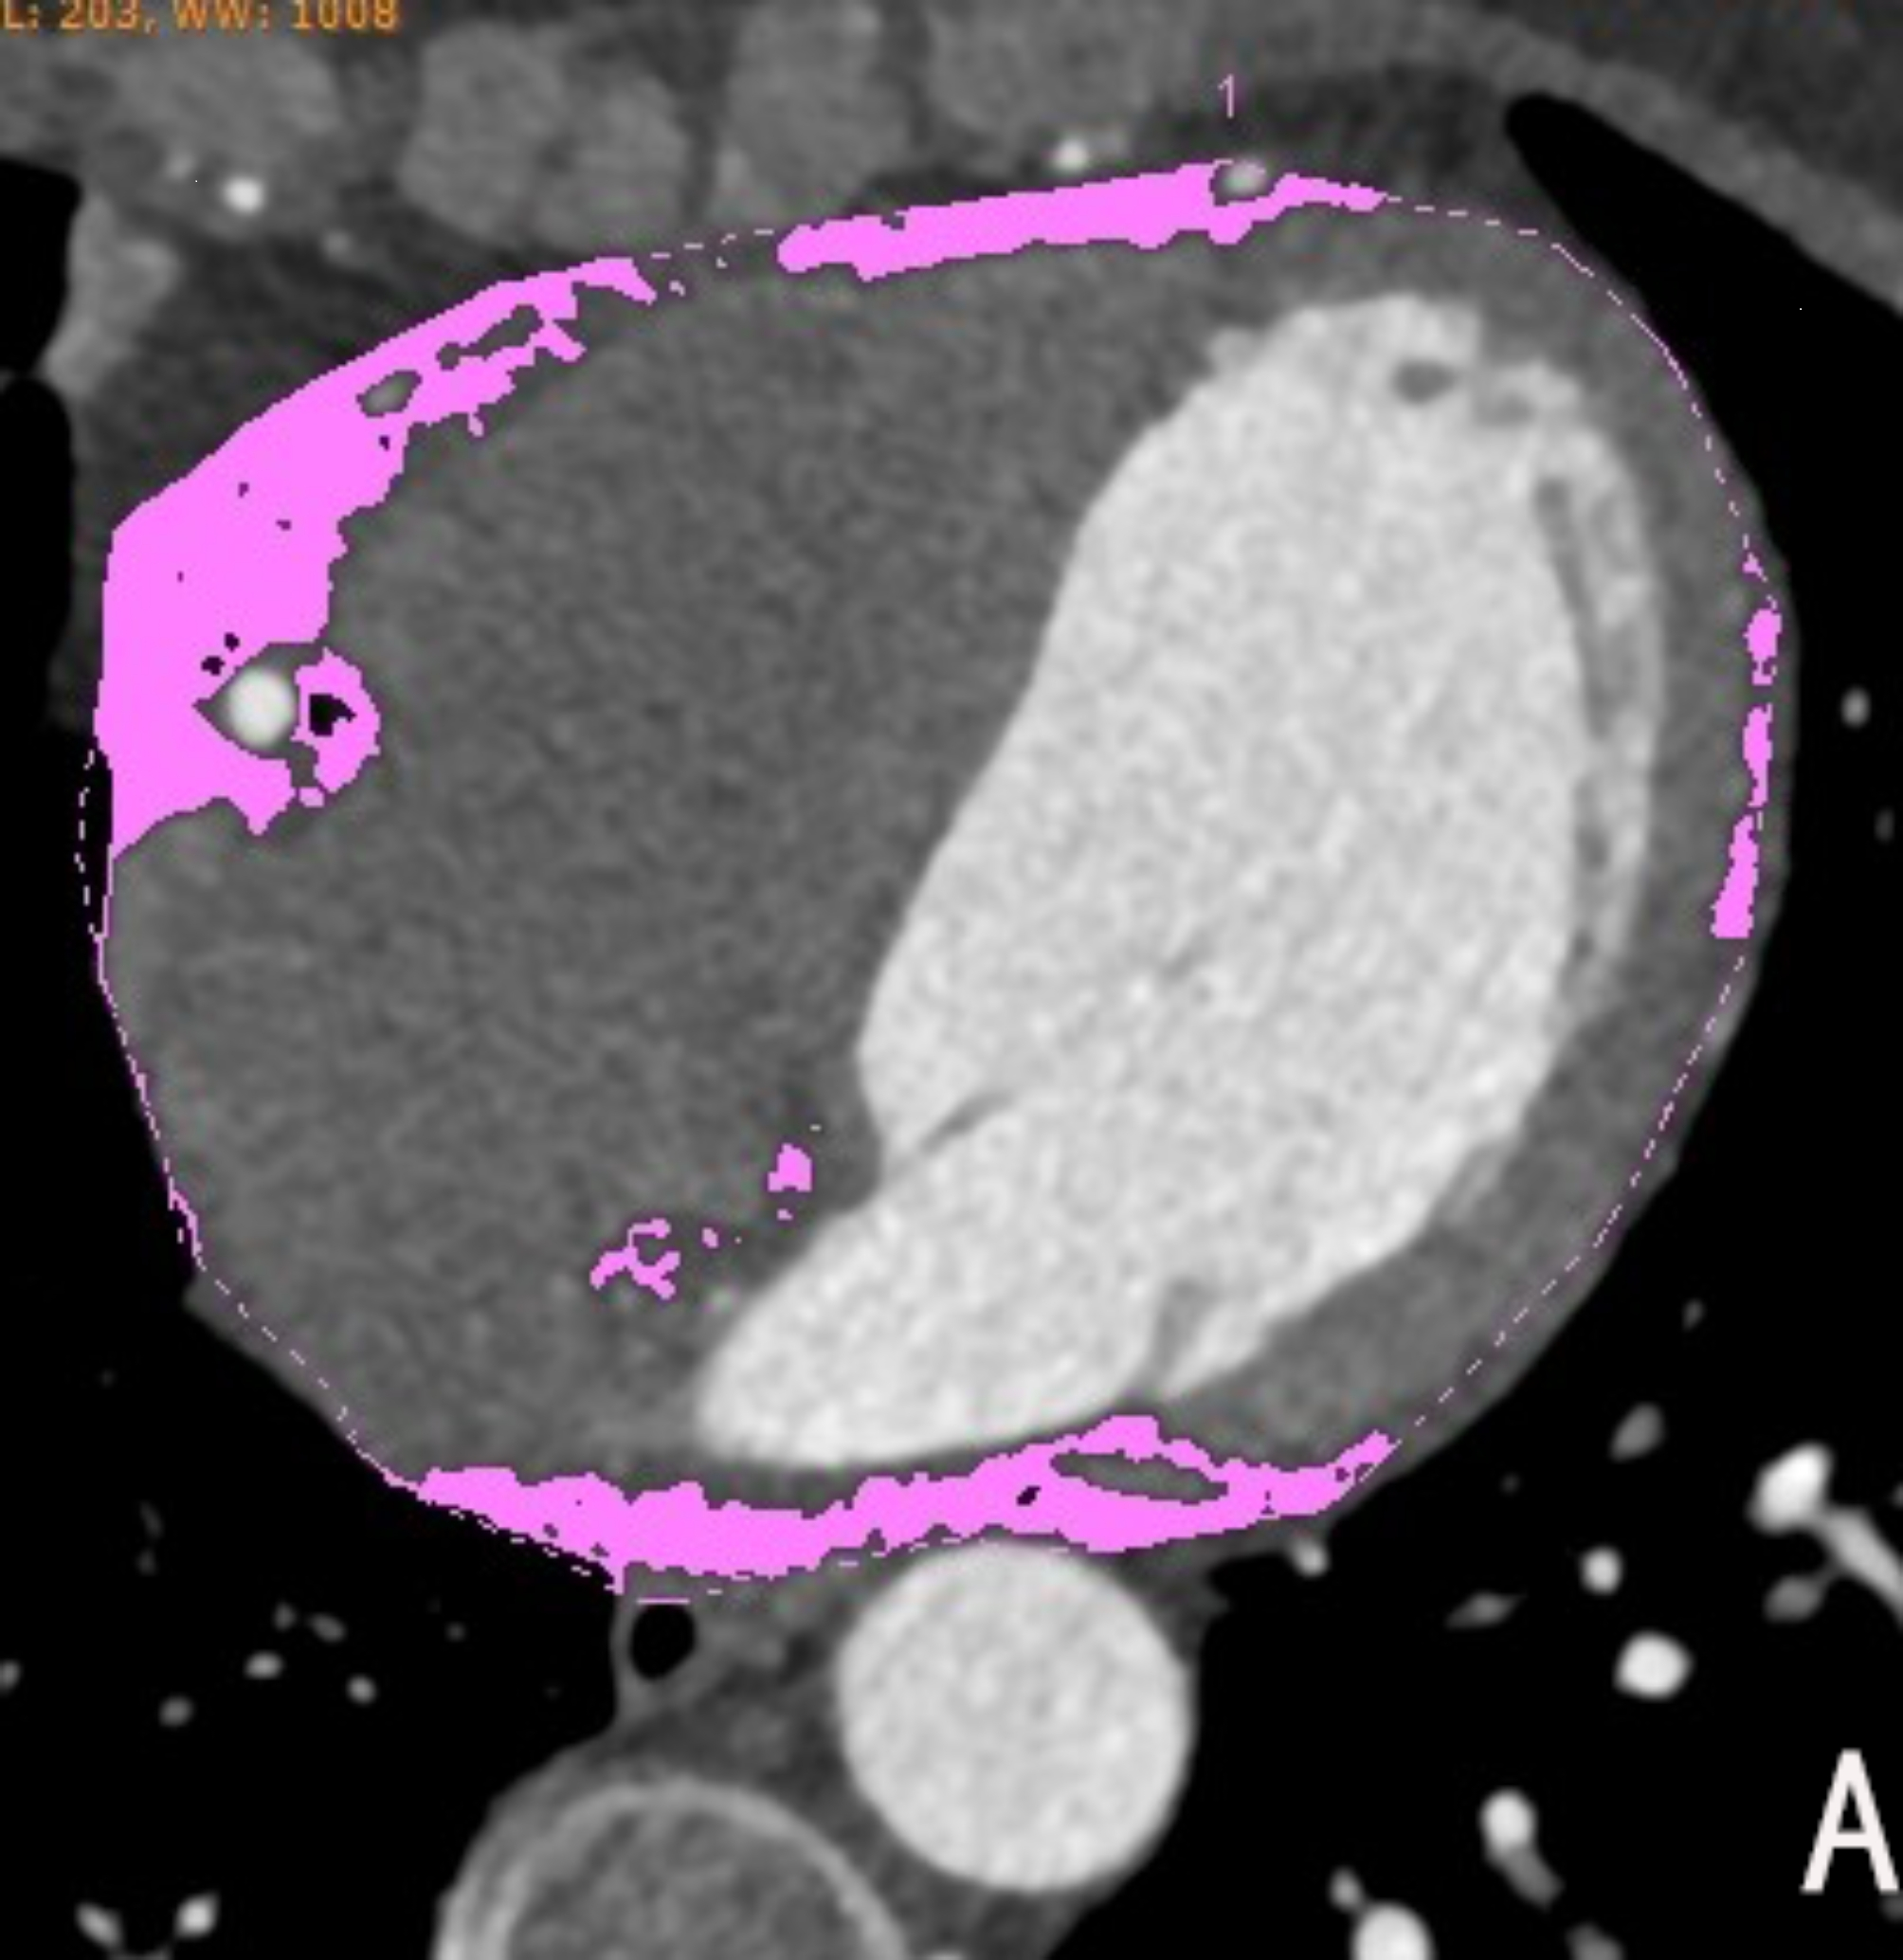

EAT volume and density measurement diagram. (A) Manual delineation of epicardial adipose tissue boundaries layer by layer, with the pink area showing the range of epicardial adipose tissue that meets the fat threshold; (B) EAT volume and average density values automatically calculated using Volume software.